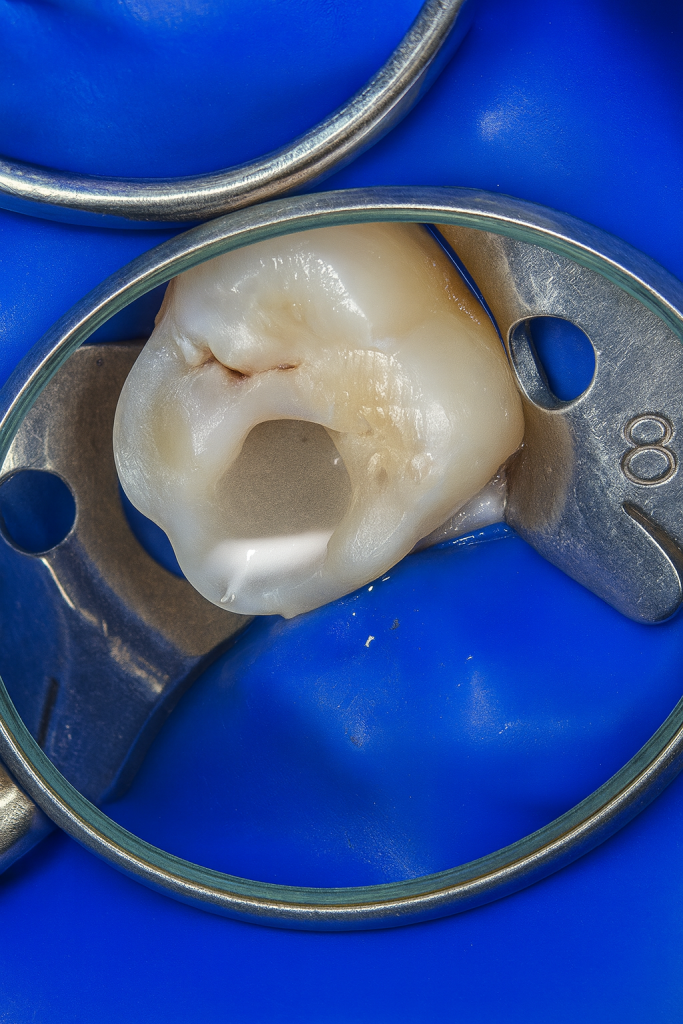

5. Post-Endo Biomimetic Cuspal Coverage

The access cavity was conditioned for adhesive restoration:

- Dentin reinforced with GC EverX Posterior.

- Enamel rebuilt using Tokuyama Estelite Sigma Quick in cusp-by-cusp layering.

- Final finishing and polishing achieved with Enhance & PoGo system, yielding lifelike morphology and high gloss. (Fig 7–8)

Fig 7–8: Post-Endo cuspal coverage composite restoration and final occlusal view.